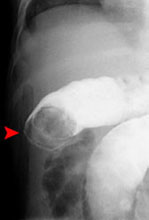

Intussusception

is the telescoping of one portion of the bowel into another. For example,

the terminal ileum could invaginate into the colon. Idiopathic incidences

may be seen following viral illness with hypertophy of Peyer's patches

in the terminal ileum. Age of presentation is usually 3 months to 24 months.

Pathologic intussusception is associated with a lead point such as a tumor, inspissated feces (cystic fibrosis) or lymphoma, often in older child greater than age 2. Symptoms include crampy abdominal pain, bloody stools, and vomiting. Treatment is fluoroscopically

guided reduction with air or fluid enema or surgery if unreducible. At our institution an air enema is first performed followed by surgery if this method is unsuccessful. |